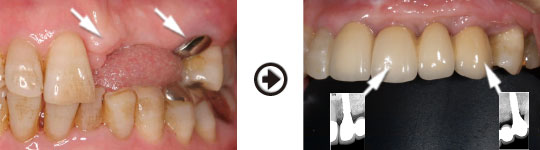

前歯の骨が薄い場合でも治療回数と期間はかかりますが、予知性の高いインプラント治療が可能です。

骨を再生させた所にインプラントを植立しました

良い状態を保つため、骨の再生だけでなく歯肉を強化し、清掃しやすい環境に整えます。

骨造成をすることにより清掃性が良くなりメンテナンスしやすくなりました。